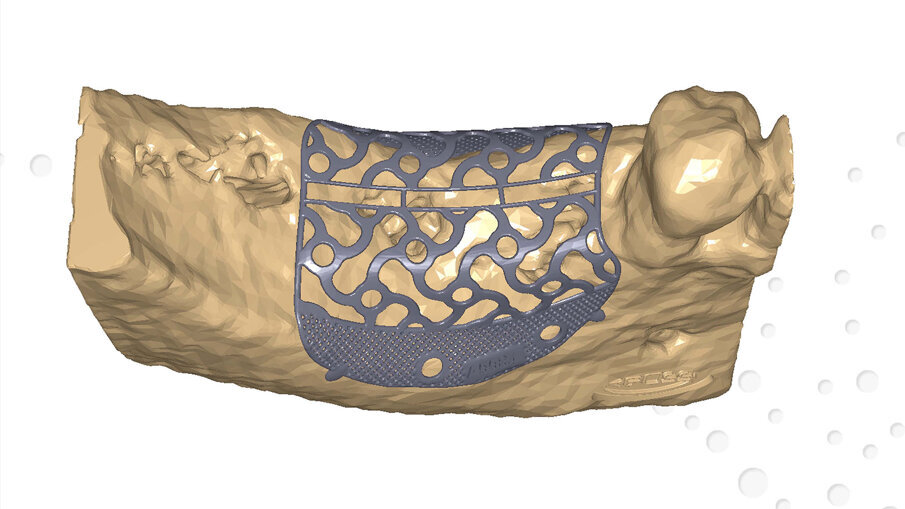

I file Dicom ottenuti, inviati all’azienda produttrice, hanno permesso di ricavare modelli tridimensionali che riproducessero in modo fedele il deficit osseo e sui quali è stata costruita virtualmente e digitalmente la griglia che, dopo approvazione, è stata prodotta. Le dimensioni mesio-distali della griglia erano di 19 mm e l’entità volumetrica del deficit osseo di 1,26 cm3 (Figg. 2a, 2b). Il piano di trattamento ha previsto un intervento di ricostruzione ossea del difetto mediante una griglia customizzata e il contestuale inserimento di 2 impianti endossei e la successiva riabilitazione protesica fissa implanto-supportata.

Figg. 2a, 2b_Modello digitale con il progetto definitivo della griglia in titanio customizzata Yxoss CBR protect.